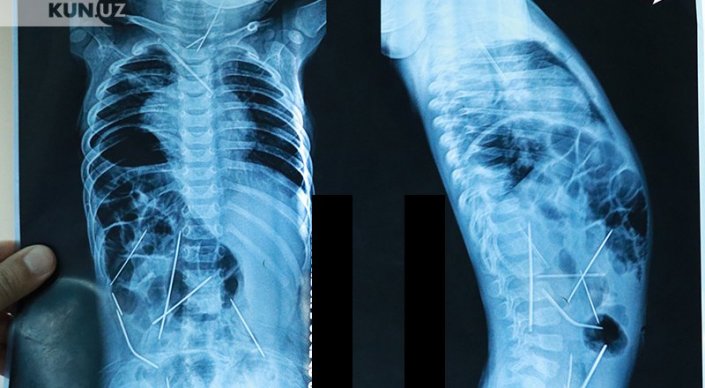

Ташкентские врачи показали годовалого мальчика, в теле которого было найдено 16 швейных иголок, сообщают "Новости Узбекистана". По их словам, сейчас его состояние оценивается как стабильное.

"При поступлении состояние ребенка оценивалось как крайне тяжелое. Это объяснялось совокупностью множества патологий: двусторонняя цветущая пневмония, абсцесс в области шеи, множественные инородные тела в грудной клетке, шее, брюшной полости, сказалась и многочасовая операция по извлечению игл", - рассказал профессор, доктор медицинских наук Хабибулло Акилов.

Напомним, маленький Азизбек Абдумаджидов поступил в Республиканский научный центр экстренной медпомощи в середине января с 16 иглами в теле. 13 иголок были удалены в ходе девятичасовой операции, три - до сих пор остаются, но, по уверению медиков, угрозы для жизни малыша не представляют, и их можно извлечь позже.

"Сегодня состояние ребенка с положительной динамикой. Сейчас он на самостоятельном дыхании, аппарат искусственной вентиляции легких работает только во вспомогательном режиме, температура нормализовалась, все анализы нормализовались. Ребенок в полном сознании. До удовлетворительного состояния, конечно, еще далеко. Но улучшения нас обнадеживают", - поделился хирург.